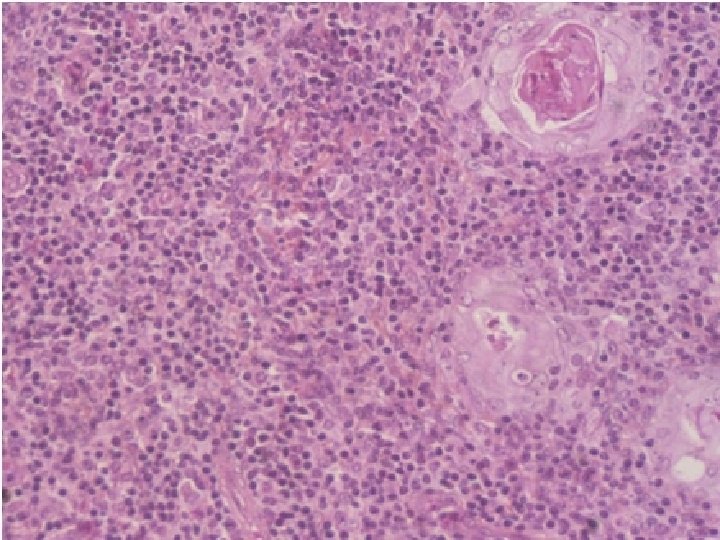

Thymus is the only discrete central lymphoid organ in humans. It produces only T lymphocyte precursors and has no lymphoid nodules. Its reticular cells derive from endoderm and produce no reticular fibers. It is the only organ containing Hassall’s corpuscles. Its age-dependent structural atrophy or involution is also unique among lymphoid organs. 2 lobes are joined and covered by a thin loose connective tissue capsule that penetrates the lobes as septa, dividing each lobe into incomplete lobules. Cortex. This is the dark-staining periphery of each lobule. Small lymphocytes predominate

Medulla. In effect, each thymic lobe has a single medulla that extends into the core of each of the lobules. The light staining of the medulla reflects the presence of more epithelial reticular cells and fewer lymphocytes than in the cortex. The spheric Hassall’s corpuscles (30 -150 m in diameter) are composed of concentric layers of flattened epithelial reticular cells. With age, cells in the core of the corpuscles may die and calcify. Functions: 1. T lymphocyte production. 2. Blood -thymus barrier. 3. Production hormone - thymosin

Histology of Thymus 40

Thymus • • n Hassal’s Corpuscles Capsule Lobules Cortex Medulla